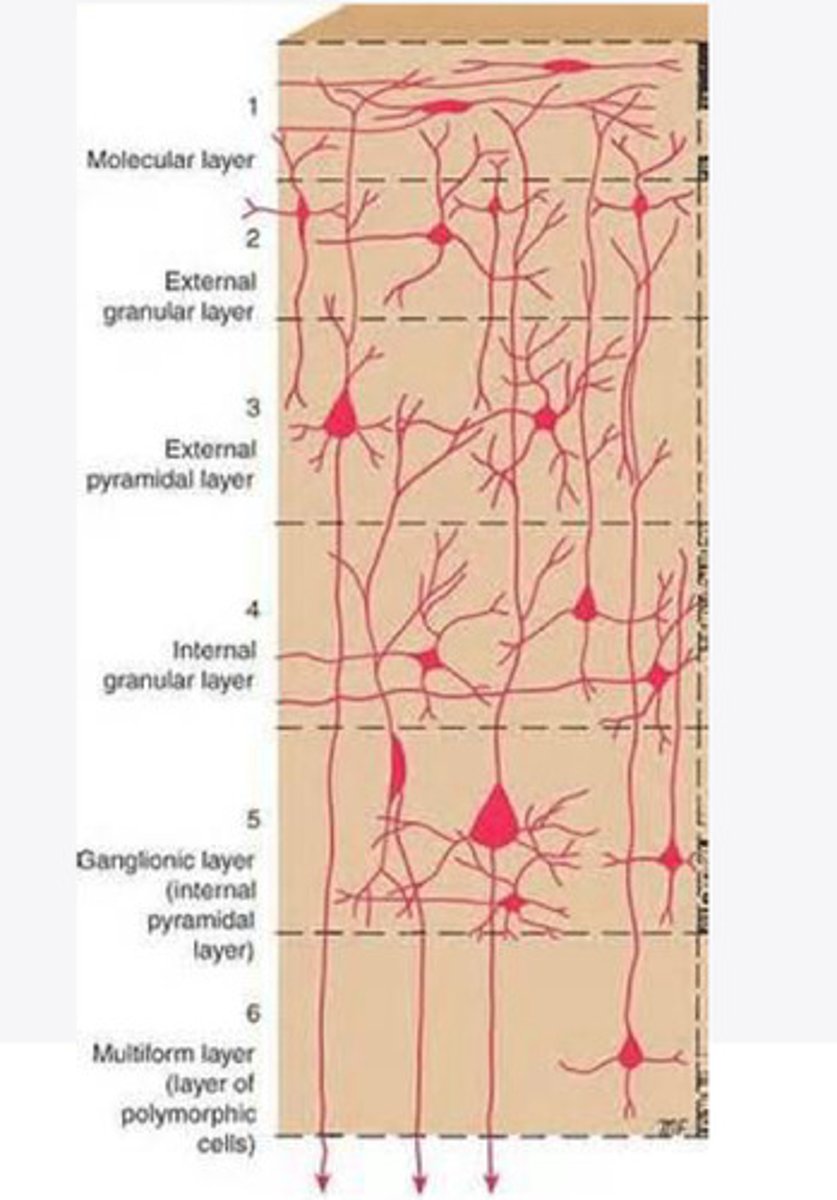

divided into 6 distinct layers, due to varying densities of cell body types within each layer

The cortex of the brain is divided into how many layers? Why is it divided into layers?

Layers of the cortex of the brain pic

2 and 4

What are the layers of the cortex that are associated with input?

3 and 5

What are the layers of the cortex that are associated with output?

molecular layer

What is the name of Layer 1 of the cortex of the brain?

very few cells

Does Layer 1 of the cortex have a lot or few cells?

receives dendrites from internal layers so it may actually function as a coordinating center where layers can communicate action

What does Layer 1 of the cortex do?

1

Every layer sends densities to Layer ____?

1

What layer serves as the "water cooler" of the brain?

external granular layer

What is the name for layer 2 of the cortex of the brain?

receives input from other cortical regions

What is the function of Layer 2 of the Cortex of the brain?

Stellate

What type of cells (stellate/pyramidal) would be most concentrated in Layer 2?

external pyramidal layer

What is the name for layer 3 of the cortex of the brain?

sends output to the other cortical layers

What is the function of Layer 3 of the cortex of the brain?

pyramidal

What type of cells (stellate/pyramidal) would be most concentrated in Layer 3 of the brain?

Layers 2 and 3

What layers are associated with association and commissural fibers?

Layer 3 - axons of cell bodies

Layer 2 - synapse into target areas in Layer 2

What part of the axons is in Layer 2/ in layer 3?

Layer 3 - external pyramidal layer

All axonal cel bodies for association and commissural fibers lie within what layer of the Cortex of the brain?

internal granular

** or called the striate cortex because it is so thick that you can see a line through this layer even in unstrained brain slides

What is the name for the 4th layer of the cortex of the brain?

receives input from the thalamus, geniculocortical layer, and other brainstem areas

What is the function for the 4th layer of the Cortex of the brain?

very thick within the vision, auditory, and somatosensory areas

Is Layer 4 thick or thin within SENSORY areas of the cortex?

Internal pyramidal

What is the name for Layer 5 of the cortex of the brain?

sends axons to the brainstem (corticobulbar) and spinal cord (corticospinal)

What is the function of Layer 5 of the cortex of the brain?

in motor areas of the cortex?

Where is layer 5 very thick in the brain?

the frontal lobe -- very motor heavy

What lobe of the brain will have a thick layer 5 of the cortex of the brain?

the multiform layer

What is the name of layer 6 of the cortex of the brain?

-sends axons back to the thalamus through corticogeniculate fibers

-modulates what information the thalamus sends to the cortex to control the strength of the signal received and modulate what you pay attention to

What is the function of layer 6 of the cortex of the brain?

no

Is layer 6 a motor layer?